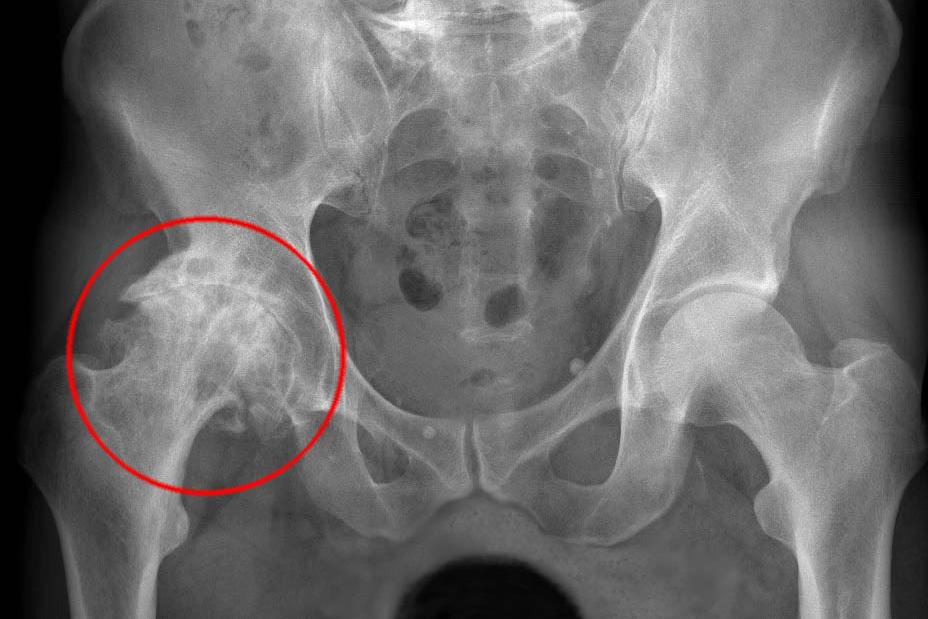

Rentgenový snímek artrózy kyčle | Foto: Fakultní nemocnice Plzeň

Kyčelní kloub je největší kloub v lidském těle a je tvořen spojením kosti stehenní s kostí pánevní. Je to kloub jednoduchý, tedy složený pouze ze dvou kostí, ale díky silným vazům, které kostní spojení obklopují, zároveň také nejpevnější. Totální endoprotéza kyčelního kloubu, zvaná též artroplastika či aloplastika, je operace, při které je nahrazen celý kloub či jeho část cizím materiálem.